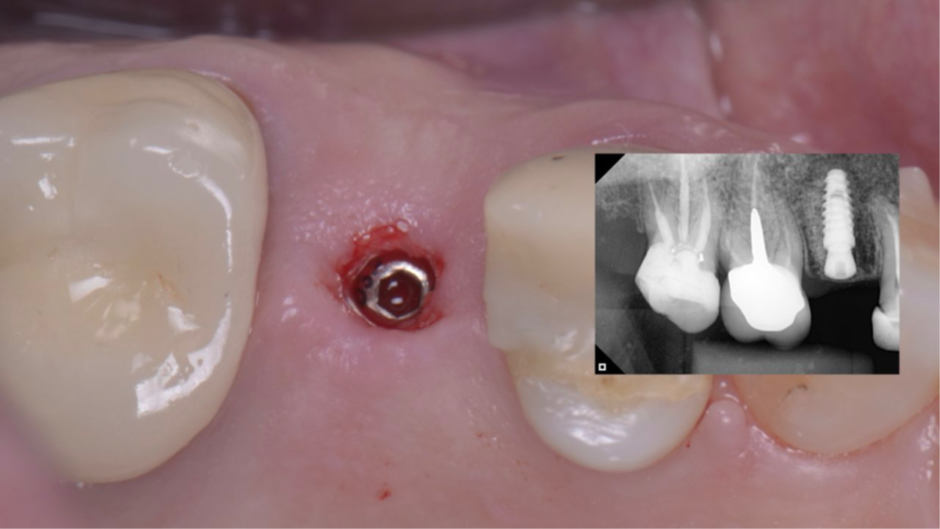

Após o planejamento virtual no programa Exoplan – Exocad (Figura 3) e confecçãode uma guia cirúrgica prototipada, foi realizada uma cirurgia guiada por computadorImplaguide 3.5/4.0 e instalado um implante Due Cone 3,5x9mm (Figura 4). Foi instalado também um cicatrizador de 3,5×2,5 (Figura 5). Após quatro meses de cicatrização, o implante estava com o cicatrizador aparente na mucosa (Figura 6).

Figura 5 – Cicatrizador de 3,5×2,5 e RX de controle imediato.

Figura 6 – Pós-operatório de quatro meses.